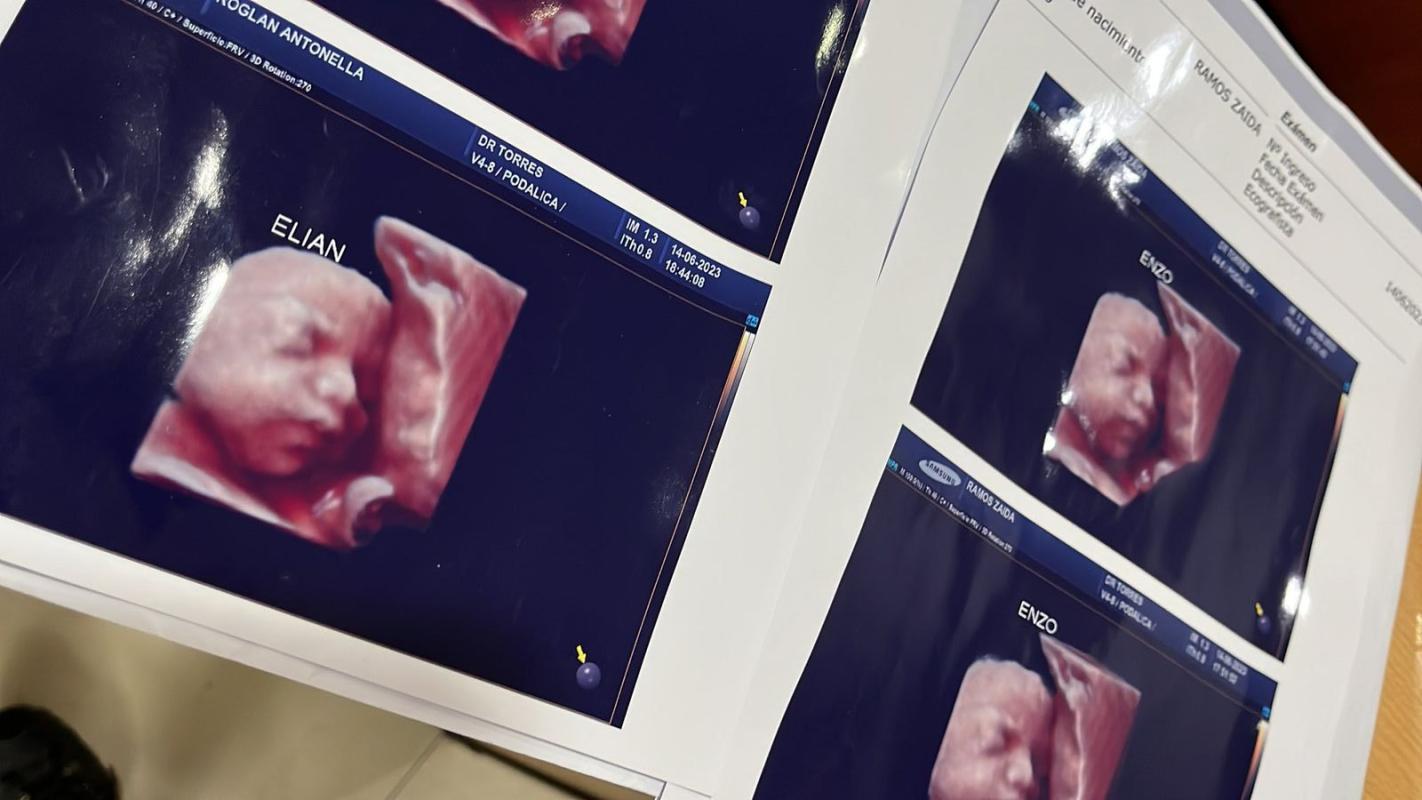

Denuncian que clínica usaba foto de una misma ecografía 5D para todas las embarazadas: caso salió a la luz en redes sociales

En las últimas horas varias mujeres denunciaron a través de las redes sociales que una clínica privada de Formosa, en Argentina, realizaba ecografías 5D y les entregaba las mismas imágenes a todas sus pacientes.

A los pocos minutos, Antonella Roglan reconoció la imagen de quien creía que era su hijo. A ella luego se sumaron otras, que coincidieron en una cosa: todas tenían la misma foto de la ecografía, pensando que el de la imagen era su hijo.

"Ese es mi bebé!!", comentó una sobre la ecografía que publicó otra embarazada. "Siiiii, es la misma", le respondió. Esta "coincidencia" desató una serie de intercambios y comparaciones que permitió descubrir el engaño.

"Por ahora somos tres mamás a las que una clínica ESTAFÓ con una foto de un bebé que no es el nuestro", reclamó Roglan en su cuenta de Twitter junto a las ecografías falsas, según consignó TN.

Aunque en las ecografías que difundió esta última correspondía supuestamente a niños, las mismas imágenes también entregaban a embarazadas que esperaban niñas. "Mi sobrino tiene 4 años y tenemos la misma ecografía en un cuadro en el modular", contestó una joven. Otra respondió: "Keeeeeeeeee!!! No te lo puedo creer. ¡Me muero literal, tengo el mismo! Quiero llorar".